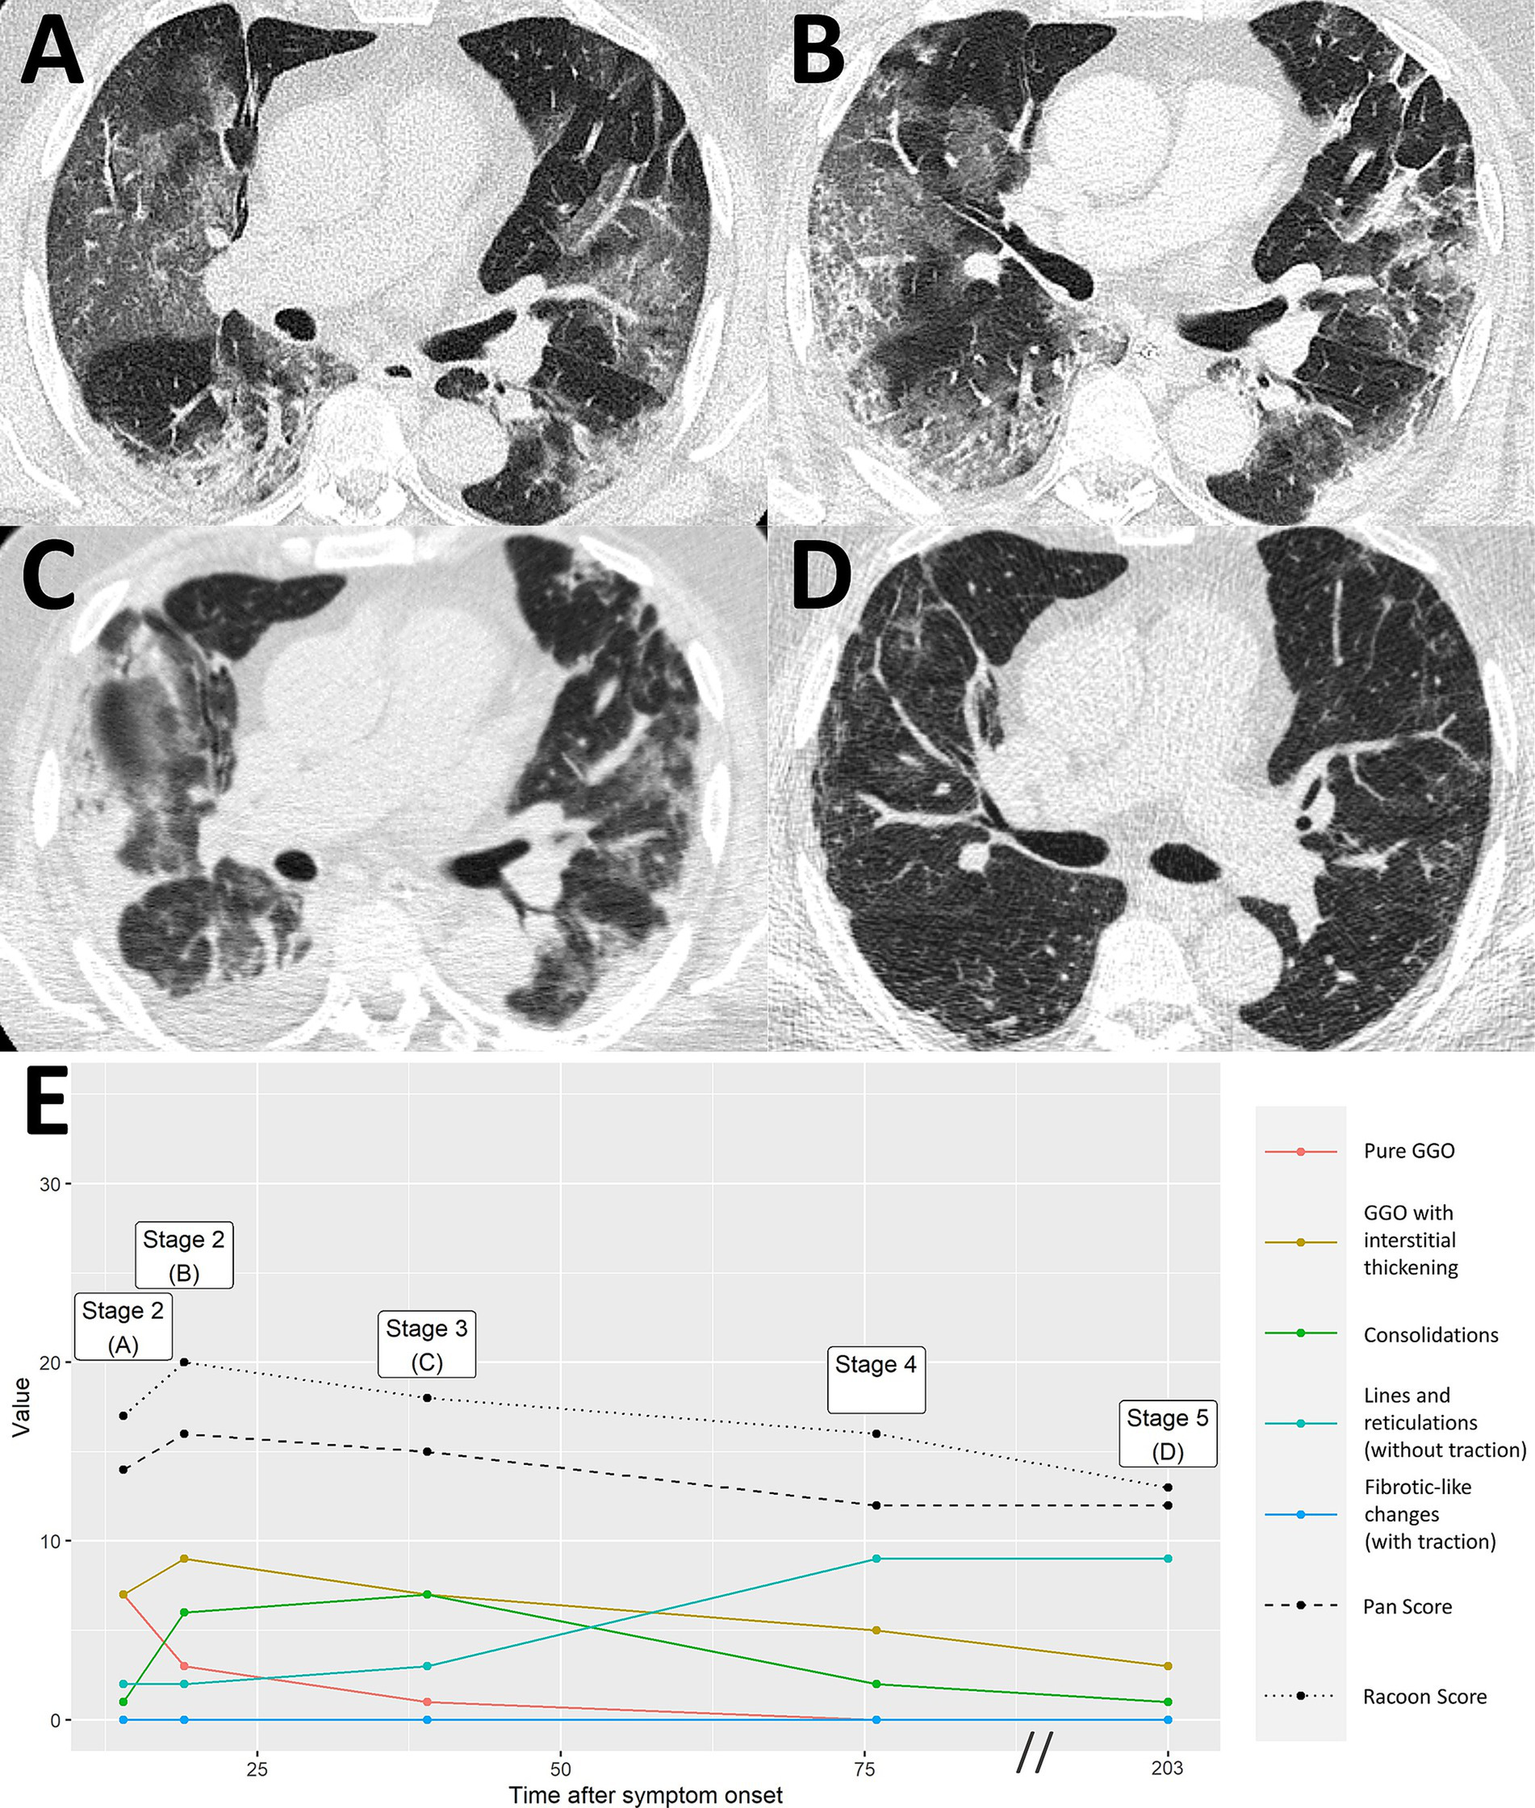

Severe COVID-19 pneumonia with residual imaging findings after >6 months follow-up. A 64-year-old male patient presented at the hospital 14 days after symptom onset, suffering from headaches and difficulty breathing. Chest CT demonstrated extensive ground glass opacities (GGO) with beginning interstitial thickening, consistent with progressive stage COVID-19 pneumonia [A, RVPS = 17 (7/7/1/2/0); stage 2]. Another chest CT 19 days after symptom onset reported an advance of the pneumonia to predominantly interstitial pathology and less ground glass [B, RVPS = 20 (3/9/6/2/0); stage 2]. Peak stage COVID-19 pneumonia with maximum consolidation was reached at 39 days after symptom onset [C, RVPS = 18 (1/7/7/3/0); stage 3]. Follow-up imaging on day 203 after symptom onset showed increasing linear opacities and fine parenchymal bands, yet no fibrotic-like changes with traction [D, RVPS = 13 (0/3/1/9/0); stage 5]. The subscores of the RVPS enable appreciation of such a typical time course of COVID-19 pneumonia, which is demonstrated in (E): Early and progressive stages are dominated by GGO and interstitial pathology (red/yellow), followed by a maximum of consolidation in peak stage (green), and eventually formation of linear opacities in resorption and post-COVID-19 stages (turquoise). RVPS, RACOON Viral Pneumonia Score; GGO, ground glass opacities.

Figure 6